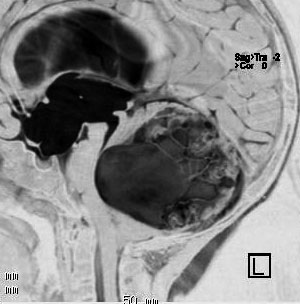

思春期の女の子にできた小脳腫瘍です。とても大きく見えますがほとんどが水たまり(のう胞といいます)。第4脳室が腫瘍で圧迫されて閉塞性水頭症になりました。のう胞の中に出血がありますが毛様細胞性星細胞腫では腫瘍内出血をしばしば見ます。右の写真で脳室が大きくなっています。こんなに大きいのに小脳症状は全くなくて,頭痛と嘔吐が症状でした。

赤で塗ったところだけが毛様細胞性星細胞腫です。これを取れば治ります。簡単な手術ですし後遺症も残りません。